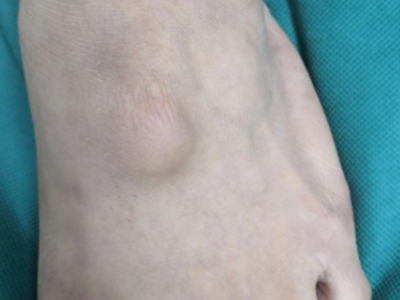

腱鞘囊肿是关节附近的一种囊性肿块,常见于女性和青少年,好发于腕关节掌侧、背侧及足背处,表现为缓慢增大的圆形或椭圆形肿块。本病的病因不清,可能与慢性损伤、结缔组织黏液退行性变有关,可进行保守治疗或手术治疗。

腱鞘囊肿常表现为腕关节掌侧、背侧及足背处的肿物,偶见于手指掌指关节及近侧指间关节处。腱鞘囊肿生长缓慢,较小时无症状,长大到一定程度活动关节时有酸胀感。检查可见0.5-2.5cm的圆形或椭圆形肿物,表面光滑,不与皮肤粘连,扪之如硬橡皮样实质性感觉。囊颈较小者略可推动,囊颈较大者不易推动,重压有酸胀痛,用粗针头穿刺可抽出透明胶冻状物。